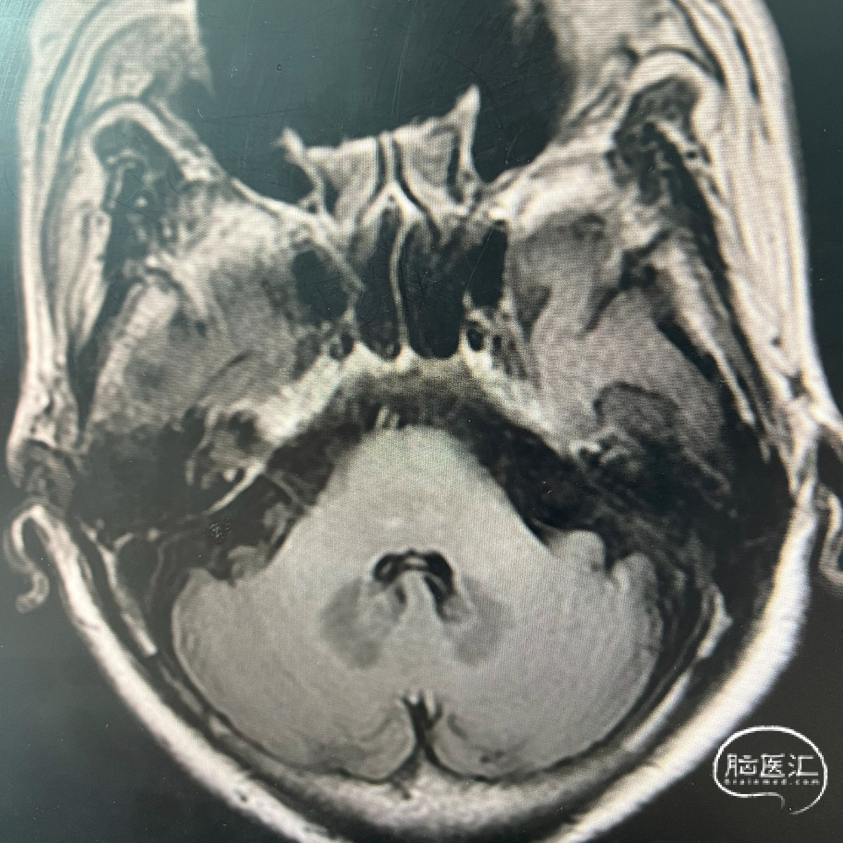

术前DWI

影像学表现: